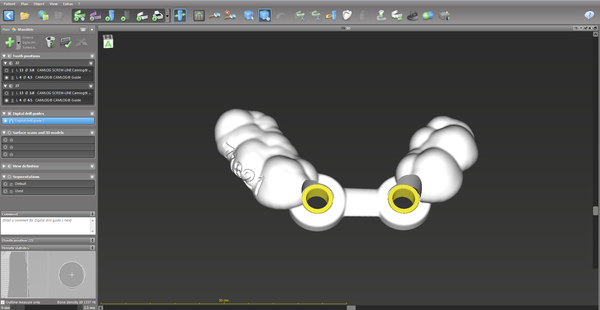

- Design and place sleeves.

- Design surgical guides.

- Export the surgical guide design as STL to be 3D printed.